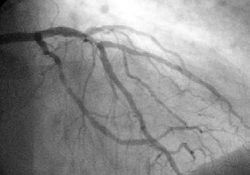

Коронарная ангиограмма (Coronary angiogram)

Коронарография — рентгеноконтрастный метод исследования, который является наиболее точным и достоверным способом диагностики ишемической болезни сердца (ИБС), позволяя точно определить характер, место и степень сужения коронарной артерии.

Этот метод является «золотым стандартом» в диагностике ИБС и позволяет решить вопрос о выборе и объёме проведения в дальнейшем таких лечебных процедур как баллонная ангиопластика (angioplasty (англ.)русск.),стентирование и коронарное шунтирование.

Во время коронарографии интервенционный кардиолог вводит водорастворимое рентгеноконтрастное вещество последовательно в левую и правую коронарные артерии, используя для этого ангиографические катетеры. При каждом таком введении рентгеноконтрастное вещество быстро заполняет просвет артерии на всем ее протяжении. В потоке рентгеновских лучей туго контрастированная артерия отбрасывает тени на детектор ангиографа, отображая информацию о своем внутреннем рельефе. Так, выполнив съемку в нескольких проекциях, можно получить наиболее полное представление об анатомии и степени поражения русла коронарных артерий. Стоит отметить, что во время исследования пациент находится в потоке ионизирующего излучения, и эквивалентная доза облучения может составить, в среднем, 2-10 миллизиверт за одно исследование.